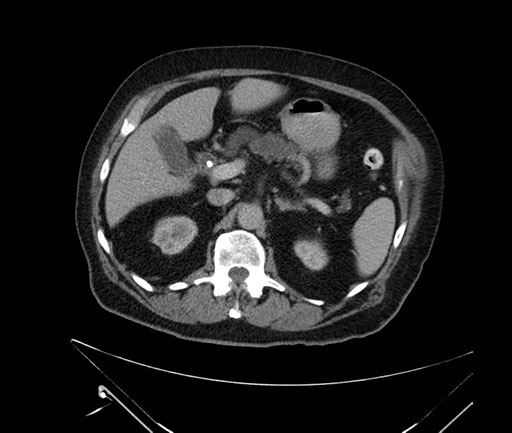

Coronal - stented